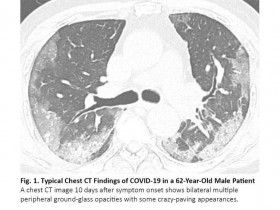

肺癌患者感染新冠肺炎COVID-19,胸部CT如何鉴别? 新药资讯

肺癌患者感染新冠肺炎COVID-19,胸部CT如何鉴别?

全球COVID-19病例已经有几千万例,死亡人数超过百万。约1%的COVID-19病例患有恶性肿瘤,1其中肺癌占相当大的比例。肺癌患者在感染COVID-19后往往会出现严重的病情,2这突出了准确、迅速...